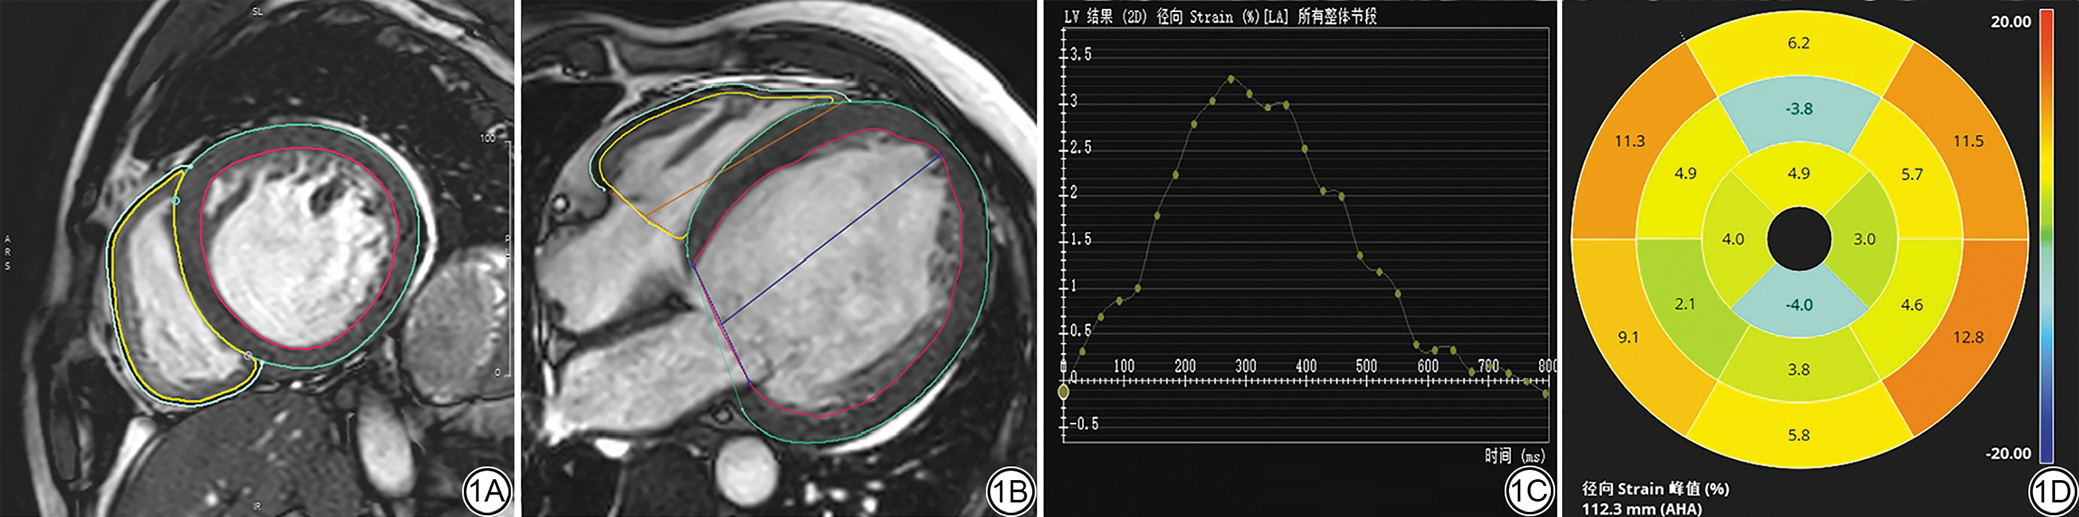

由1位具备3年CMR诊断经验的放射科医师利用CVI42软件(版本 6.2.1;加拿大,卡尔加里;Circle Cardiovascular Imaging Inc.,Calgary,Canada)在应变模块中分析左心室(left ventricle, LV)和右心室(right ventricle, RV)长轴及短轴电影图像,软件自动识别左心室舒张末期及收缩末期的心内膜和心外膜轮廓,若出现偏差则手动修正,然后逐层勾画右心室最佳心内膜及心外膜边界,然后运行软件程序,获得心室整体和心尖部(Apical)、心室中部(Mid)、基底部(Basal)的径向应变(global radial strain, GRS)、周向应变(global circumferential strain, GCS)、纵向应变(global longitudinal strain, GLS)以及相应的应变曲线和牛眼图(图1)。

图1  CMR双心室心肌应变勾画图、应变曲线和牛眼图。1A和1B分别为双心室舒张期短轴和长轴视图,红色线条为LV内膜轮廓,绿色线条为LV外膜轮廓,黄色线条为右心室内膜轮廓,蓝色线条为右心室外膜轮廓;1C为LV径向应变曲线;1D为LV径向应变牛眼图,比色卡范围为+20%至-20%,越靠近橙色(+20%)心肌收缩功能越好,越靠近蓝色(-20%)心肌功能受损越严重,AHA标准16分段模型测量出的左心室舒张末期长轴长度为112.3 mm。CMR:心脏磁共振;LV:左心室;AHA:美国心脏协会。

Fig. 1  CMR Biventricular myocardial strain analysis: delineation, curves, and bull´s-eye plot. 1A and 1B: Diastolic short-axis and long-axis views of both ventricles. The red line indicates the contour of the inner membrane of the LV, the green line indicates the contour of the outer membrane of the LV, the yellow line indicates the contour of the inner membrane of the right ventricle, and the blue line indicates the contour of the outer membrane of the right ventricle. 1C: Global LV radial strain curve. 1D: Global LV radial strain bullseye map, with the color scale ranging from +20% to -20%. The closer to orange (+20%), the better the myocardial contractility; the closer to blue (-20%), the more severe the myocardial function impairment. The LV end-diastolic long-axis length measured by the AHA standard 16-segment model is 112.3 mm. CMR: cardiac magnetic resonance; LV: left ventricle; AHA: American Heart Association.